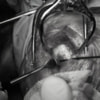

関節穿刺を行い、好中球はなく、少数のマクロファージや滑膜細胞が認められるました。膝蓋骨脱臼および前十字靭帯断裂による退行性の関節炎を疑い、関節鏡検査を実施いたしました。関節鏡検査では、重度の滑膜炎および前十字靭帯の完全断裂が認められました。内外側とも半月板に損傷は認められませんでした。

断裂前十字靭帯の除去を行いました。外側方向からのテンションが著しく、外側広筋と膝関節外側支帯の解放を行いました。膝関節伸展機構の著しいアライメント異常が認められたため、脛骨粗面転移術を実施しました。

写真の膝関節の垂直線を綿棒の木柄が表しており、遠位の脛骨粗面との位置関係が平行ではありません。

転移側の骨床は犬種特有の変形した表面であったため、転移後の骨片の圧着状態が改善するように変形表面をラウンドバーにて切削しました。滑車溝の著しい低形成が認められたため、滑車溝形成術を実施いたしました。

切断された関節包の縫縮を行いました。前十字靭帯断裂後の不安定性と内旋を解消するために、人工靭帯(fiber wire)によるラテラルスーチャー法を併用し安定化を図りました。

術後、整形外科学的検査における脛骨圧迫テストや前方引き出し兆候は認められませんでした。